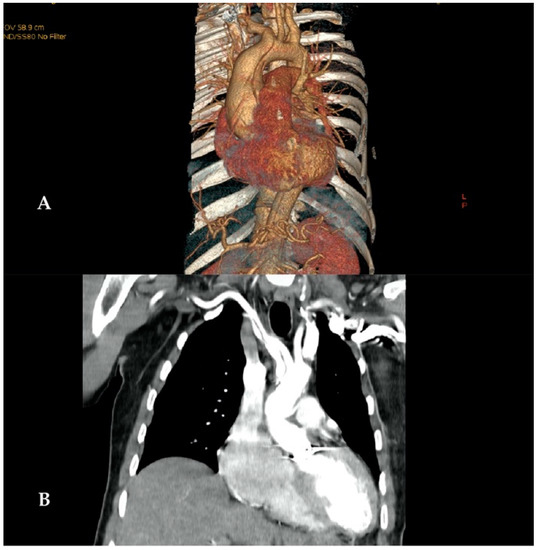

1. Introduction

2.1. Surgical Technique

3.4. Long-Term Results and Fate of the Innominate Artery